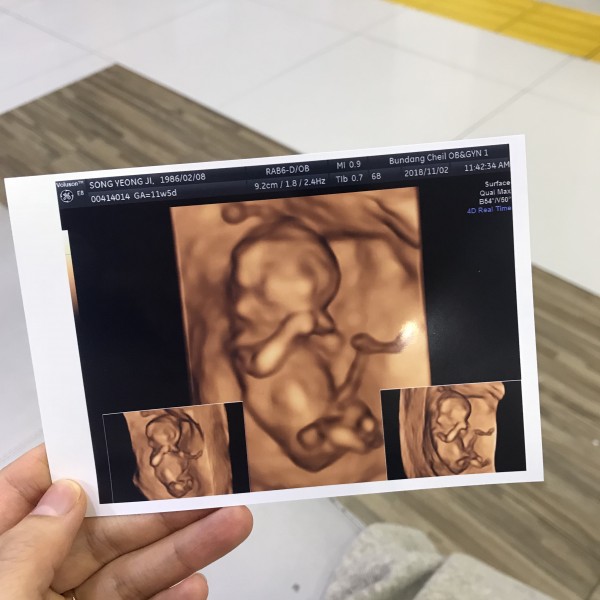

2019-04-29안녕하세요. 이현준님, 먼저 아내를 생각하는 마음이 가득 담겨진 편지라 더욱 더 따뜻함이 전해지는 것 같습니다. 더불어 예쁜 사진들과 이은성 과장님을 비롯한 많은 직원분들 한 분 한 분을 잊지 않고, 이렇게 정성스럽게 써주신 편지에 본원의 모든 직원들이 놀람과 감동을 크게 느켰습니다. 본원의 모든 선생님들이 친절한 것 같다는 말씀도 정말 감사드립니다.^^예쁘게 완성한 펠트만큼와 초음파 사진 속 현준님의 아이도 너무 사랑스럽고, 예쁩니다. 바쁘신 와중에 감사의 편지를 남겨주셔서 감사합니다. 전해주신 감사의 편지에 보답할 수 있도록 더욱 친절하고, 높은 의료 서비스로 발전하는 분당제일여성병원이 되겠습니다.